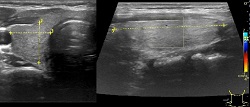

Węzły chłonne, guzki, przepukliny

Wykrywanie chorób powodujących powiększenie węzłów chłonnych. Guzki podskórne. Badanie zawartości przepuklin.

USG węzłów chłonnych-pozapalna limfadenopatia.